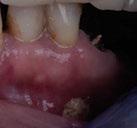

Ramos-Ríos y cols. estudiaron dos escuelas con niños de rango de edad de 6 y 12 años, en México. Para ello, se empleó un cuestionario para los padres y se obtuvo que un 6,84% padecían asma; de éstos se llevó a cabo el estudio (Tabla 1).

Tras los resultados obtenidos llegaron a la conclusión de que son muchas las patologías asociadas al asma, y no solo repercusiones sobre su salud oral, sino maloclusiones del tipo mordida abierta o paladar ojival asociadas a deglución atípica, propias de una respiración oral

Imagen cedida por la Dra. Clara Garcete, profesora de Grado y Máster de la Universidad CEU San Pablo.

también relacionada con esta patología. El pH ácido se encontró en un 96,42% de los niños y se sabe que tiene relación directa con la formación de caries. No encontraron asociaciones con xerostomía, erosión dental o candidiasis, siendo estas patologías relacionadas, al mismo tiempo, con la inmunosupresión generada por los fármacos (1).

Imagen cedida por la Dra. Clara Garcete, en Clínica Ciro.